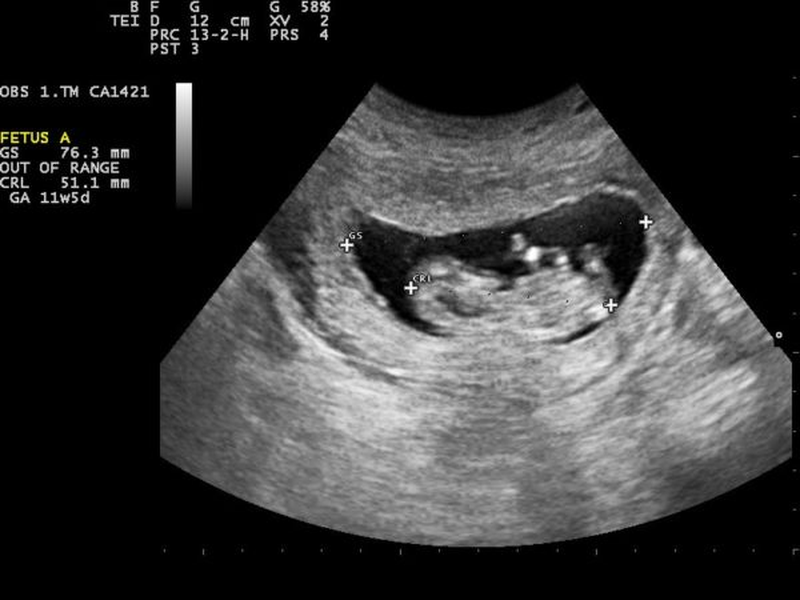

Phôi tăng kích thước ổn định theo từng tuần

Phôi ở giai đoạn sớm sẽ lớn lên rất nhanh. Chỉ số CRL (chiều dài đầu - mông) tăng trung bình 1 mm mỗi ngày trong tuần thứ 6-8. Việc siêu âm cho thấy phôi dài hơn qua từng lần kiểm tra là bằng chứng thai đang lớn lên bình thường.